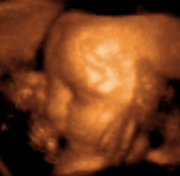

A fetus in the womb, viewed in a sonogram

"3D ultrasound" of a developing fetus at 29 weeks